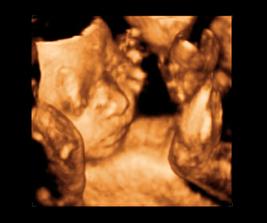

26 tt../1.4.2009/ naša paulínka je stráášne zlatá, boli sme si pozrieť na 4D utz. ..tvárila sa veľmi dôležito, až nafúkano...hehe..vôbec sa nechcela usmievať... nakoniec sa nám aj zasmiala...v brušku veľmi vyvádza, maminke dosť vytláča všetky časti telíčka, čo je niekedy aj dosť bolestivé...ale vydržíme, drobečkovi je tam určite tiež pritesno..a ešte aj stále viac a viac bude... strááášne sa na ňu tešíme🙂))